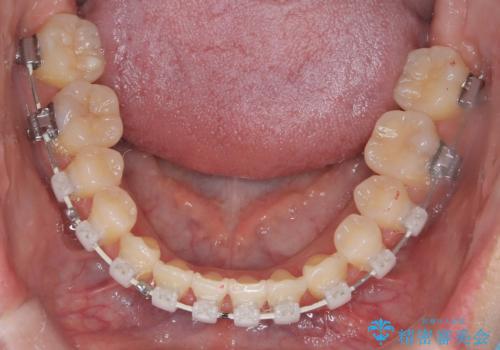

【ワイヤー矯正】一番後ろの奥歯でしか噛んでいないかみ合わせを治したい

- 審美装置

- 噛み合わせを治したいとのことで来院された患者様です。

最初は、一番後ろの奥歯でしか噛んでいない状態で、上下の前歯の先端がちょうど当たる切端咬合でした。

口腔習癖の改善及び、ワイヤー矯正にて歯列の平坦化を行うことで咬合を確立することができました。